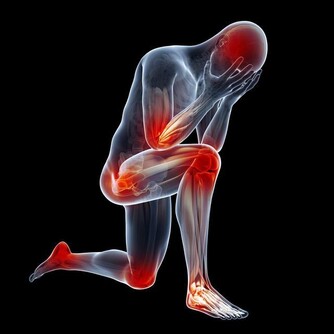

除此之外,起床後眼皮浮腫、腰酸乏力可能是腎病初期的表現,小便紅、小便時泡沫較多且持續時間長,四肢、臉上、身上的皮膚出現較多的紅點或紅斑,四肢關節酸痛等都應引起警覺。

慢性腎髒病是一個長期持續進展的過程,共分為5個時期。前3個時期中,腎臟的代償作用可以基本可以完成腎臟的功能,病人通常沒什麼不舒服。而到了第4期,腎功能的損害已經進入不可逆的階段,病人的食慾減退、貧血、血鉀高、消化道出血等症狀日漸明顯,甚至心臟等其他器官也開始衰竭。